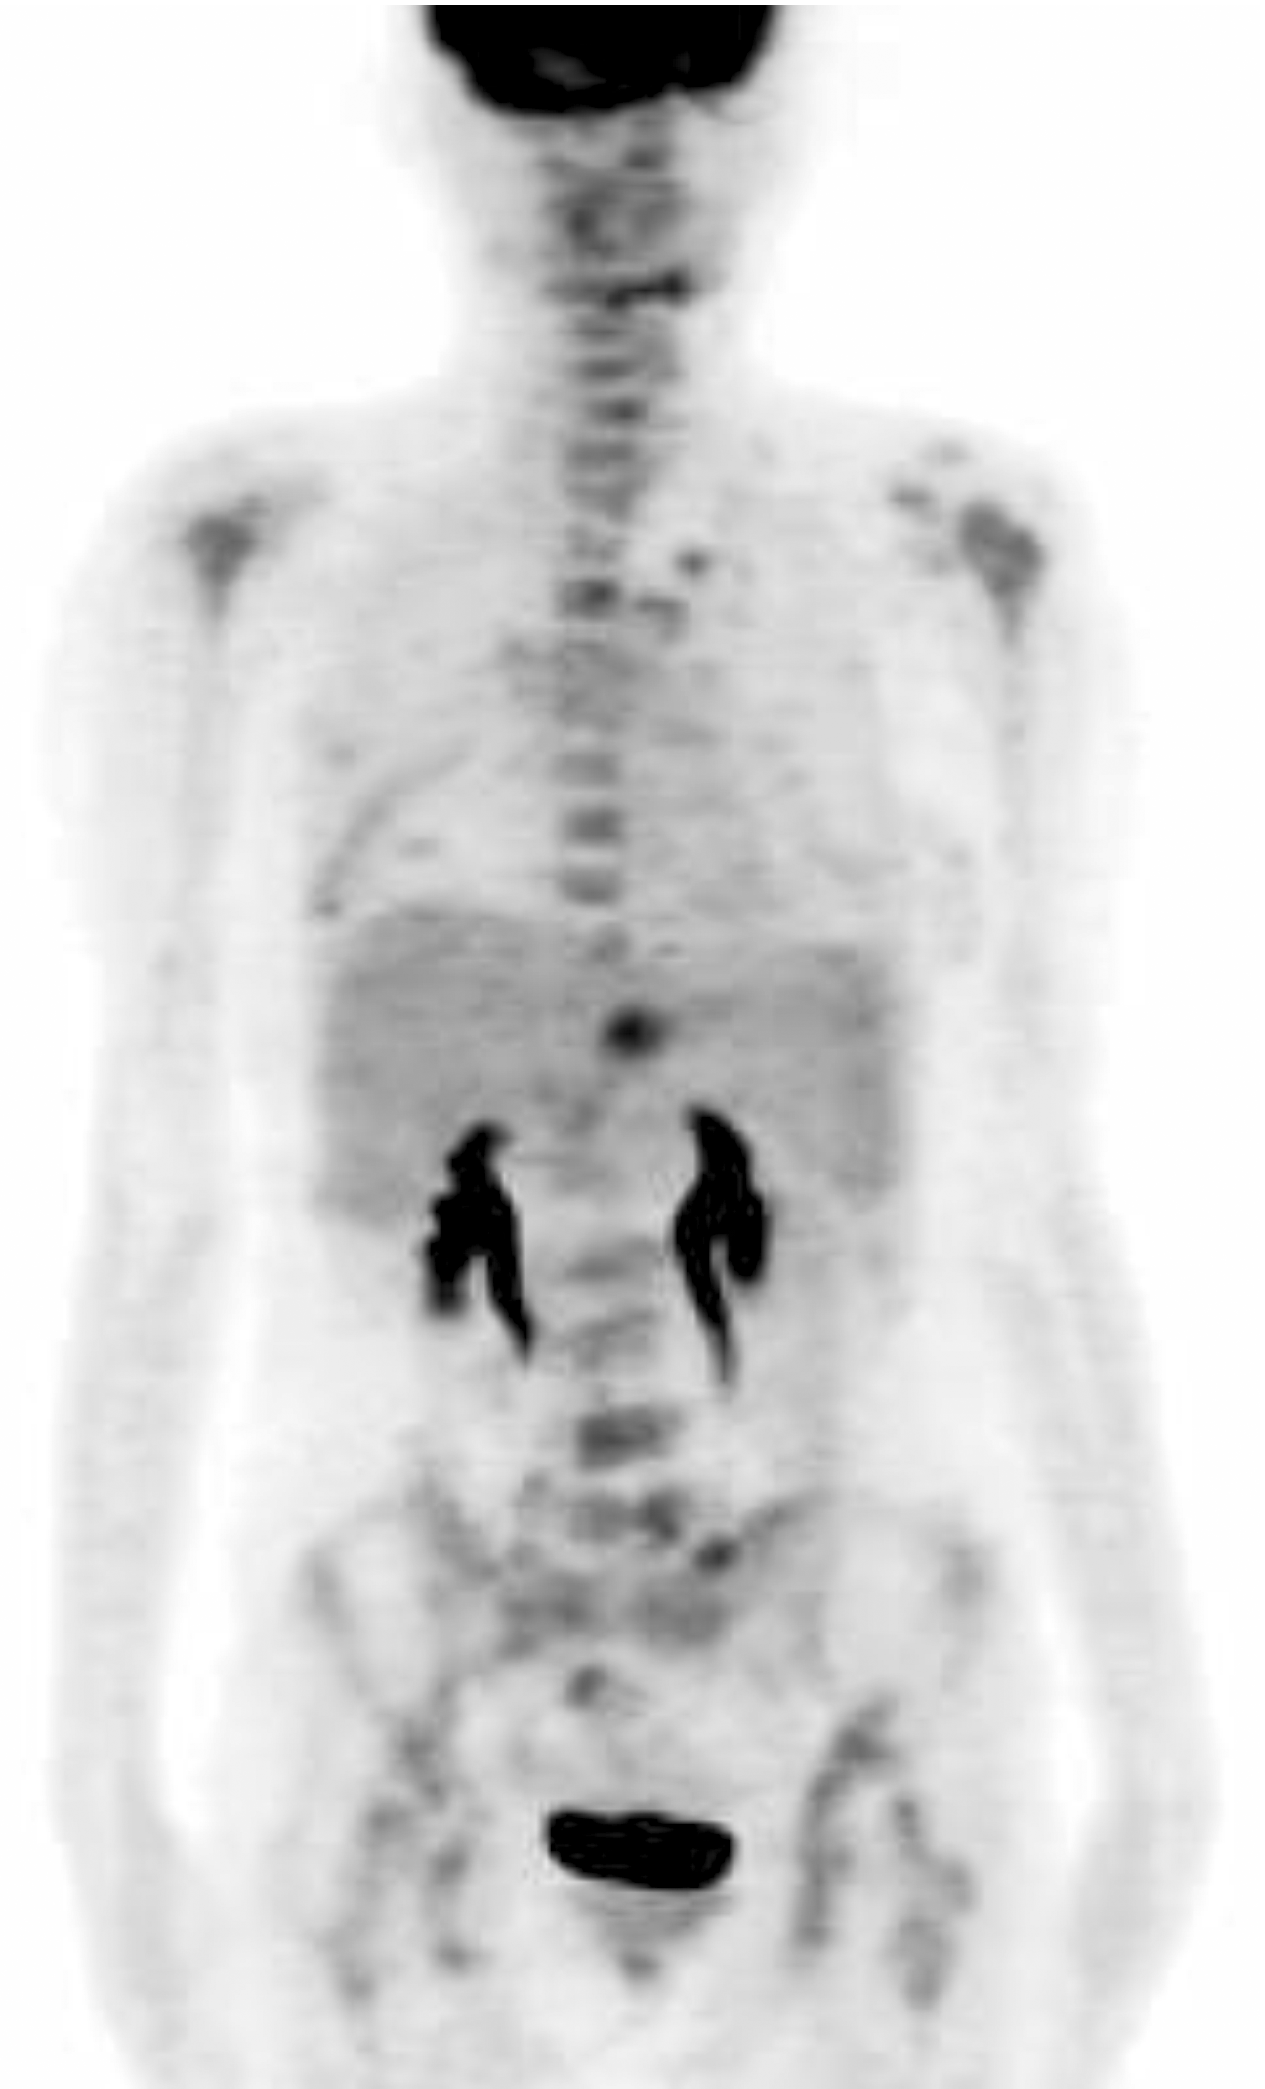

张国淳:该患者至我院治疗时局部复发及骨转移与内脏转移并存, 肿瘤负荷大, 应该考虑首选联合化疗。对于在辅助治疗中使用过蒽环类的患者, 复发转移后的一线治疗方案可以选择多烯紫杉醇联合卡培他滨(XT方案), 该方案的总有效率高于40%。该方案同时也是NCCN乳腺癌临床指引及AGO乳腺癌临床指引所强烈推荐的。因此, 我们在患者的一线治疗中采用了XT每3周方案。然而, 在化疗2个周期后我们又进行了一次PET的疗效评价, 结果显示:右侧乳腺、双肺多发结节、肝脏肿块、盆腔淋巴结及全身多处骨髓局灶性葡萄糖代谢异常增高灶, SUV较前明显降低; 与前一次本院PET影像比较, 可见新发病灶(肝脏), 见图2。那么如何评价此时的疗效呢?是否需要更换二线化疗方案?

廖宁:该患者的PET结果显示除肝脏新发病灶以外, 全身其它病灶均明显缩小, 代谢减弱。如果按照RECIST标准来衡量, 出现新病灶均应评价为疾病进展。然而, 在全身大部分病灶均明显缩小的情况下, 更换二线化疗方案是否可行?有无其它手段进行评价?

张国淳:目前对化疗效果的评价还有外周循环血肿瘤细胞(circulating tumor cells, CTC)检测这一手段。CTC检测已经被美国FDA批准为评价疗效的手段之一, 但尚未在中国正式上市。广东省人民医院乳腺科正在参与一项CTC检测用于转移性乳腺癌的多中心Ⅲ 期临床试验。因此, 该患者也加入了此研究。该患者开始一线治疗之前的CTC检测结果为185个/7.5 mL血, 而在2个周期后已经明显降低至92个/7.5 mL血。如果按照CTC检测的结果, 患者对XT方案的治疗是有效的, 不应该更换方案。因此, 我们为该患者制定了继续XT方案化疗的策略。在第4周期末时又进行了PET检查及CTC检测。PET结果显示:右侧乳腺结节、肝脏肿块局灶性葡萄糖代谢异常增高灶; 与前次PET影像比较, 原骨髓多发高代谢病灶明显减少, 葡萄糖代谢活性减低; 肝左叶转移灶缩小, 葡萄糖代谢活性减低, 提示化疗后转移瘤部分缓解, 见图3。而CTC检测的结果则显示:CTC数量为1个/7.5 mL血。因此, 在完成4个周期XT之后的疗效评价为部分缓解, 继续进行2个周期XT方案化疗。

马冬(肿瘤内科学副主任医师):转移性乳腺癌一线治疗方案的疗效评价至关重要。然而, 单纯的影像学评价有时候会出现令人困惑的情况。此时结合非影像学的检查结果进行综合考虑是一种有效的解决方法。此例患者结合CTC检测结果, 采取了继续原方案的策略, 避免了贸然更换化疗方案造成治疗上的被动, 结果表明是十分正确的。